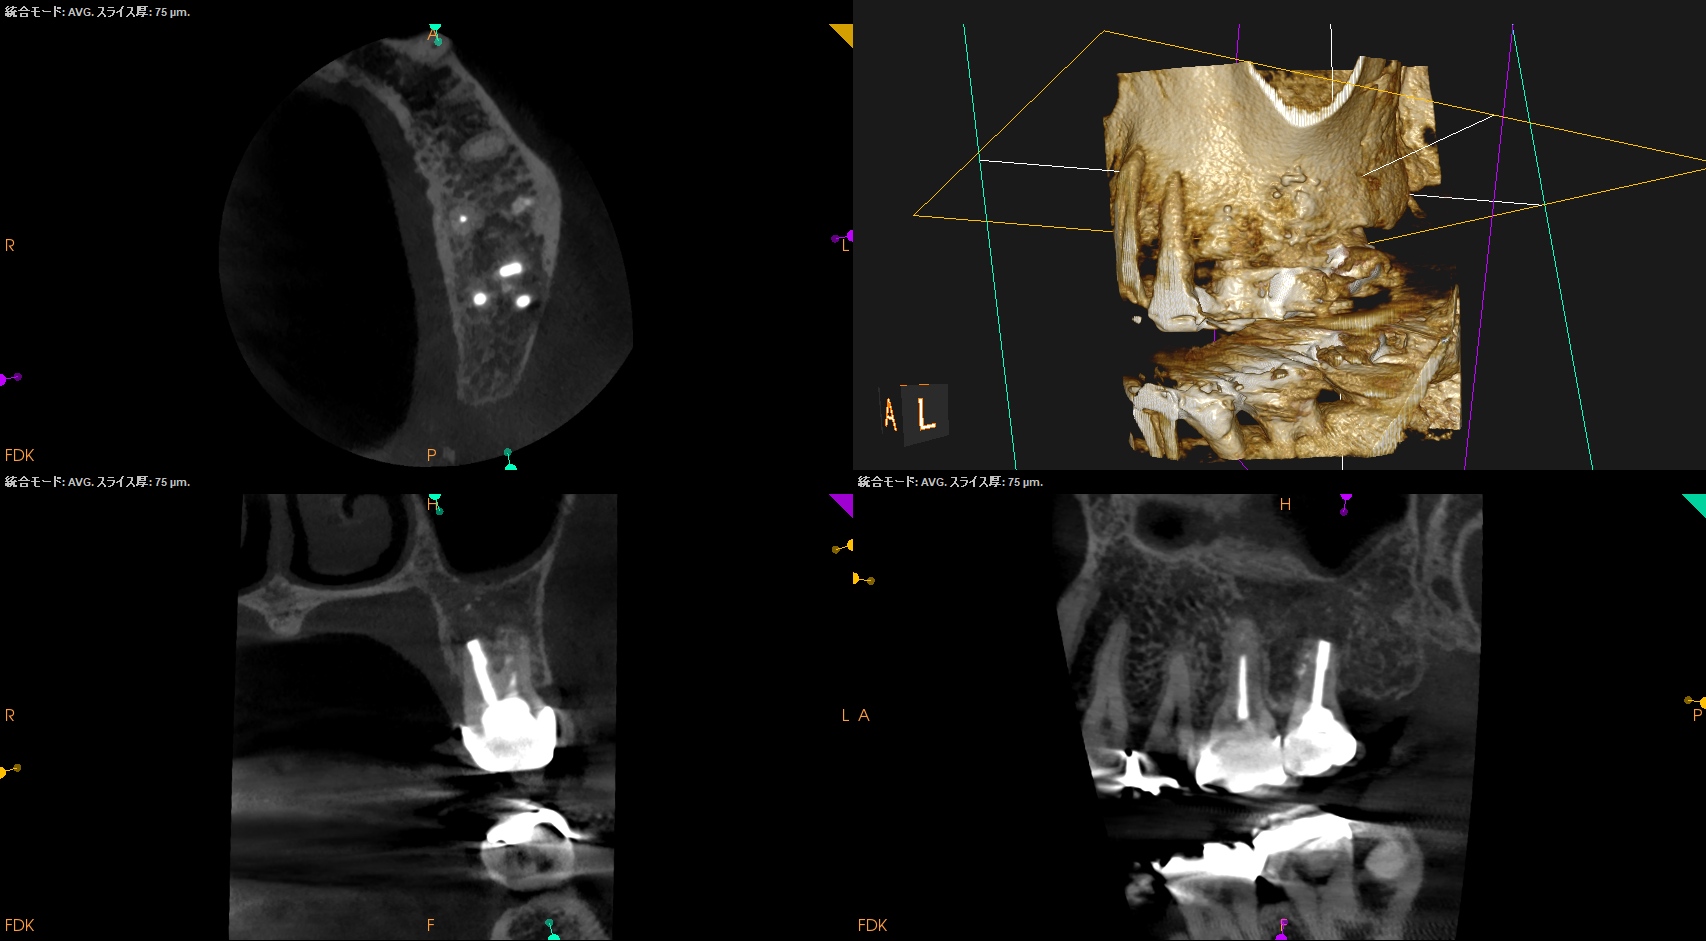

CBCT(2025.11.5)

MB

DB

P

Perforation site